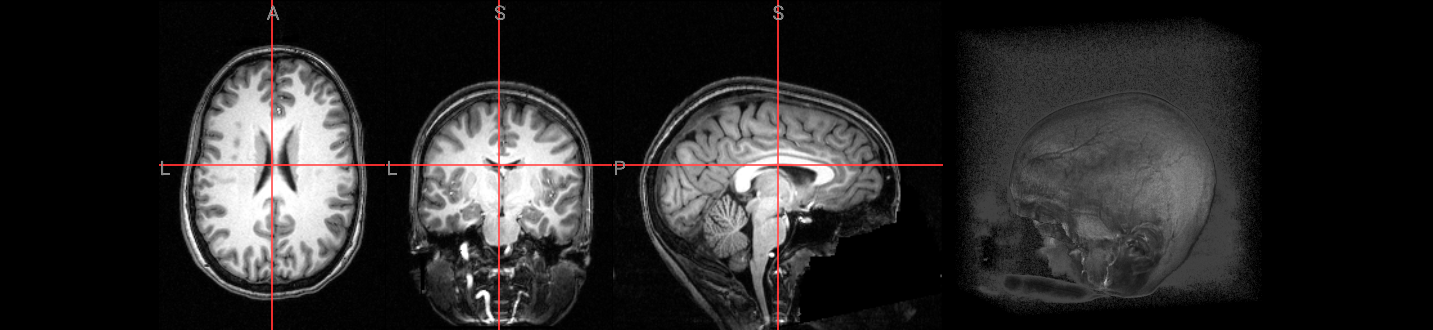

Inspecting the anatomical and functional images#

To use the AFNI graphical user interface, you would type:

afni sub-08_T1w.nii.gz

We will use ipyniivue to look at the data:

Many of the quality checks for the functional images are similar to those for the anatomical images. Look out for excessively bright or dark spots in the grey or white matter, as well as any image distortions, such as abnormal stretching or warping. A common area where slight distortion may occur is in the orbitofrontal region, just above the eyeballs.

Additionally, it’s important to check for excessive motion during the scan.

anat_image = './ds000102/sub-08/anat/sub-08_T1w.nii.gz'

func1_image = './ds000102/sub-08/func/sub-08_task-flanker_run-1_bold.nii.gz'

func2_image = './ds000102/sub-08/func/sub-08_task-flanker_run-2_bold.nii.gz'

# anatomical image

nv = NiiVue()

nv.load_volumes([{"path": anat_image}])

nv

Image(url='https://raw.githubusercontent.com/NeuroDesk/example-notebooks/refs/heads/main/books/images/afni_preproc_anat.png')